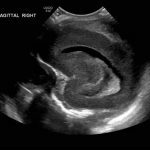

Age: 4 days (born at 24 weeks)

Sex: Male

Indication: Evaluate for germinal matrix hemorrhage

Grade 2 germinal matrix hemorrhage

Sample ReportLeft germinal matrix hemorrhage involving the caudothalamic groove and layering in the occipital horn of the left lateral ventricle without hydrocephalus (grade 2).

No abnormal brain parenchymal echogenicity or extra-axial collections.

Premature sulcation pattern.